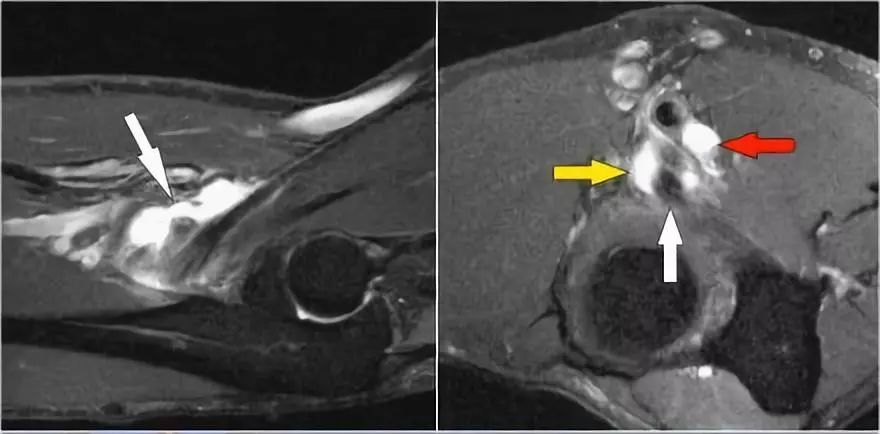

下面另一种慢性撕脱伤,被送到肿瘤外科医生,因为担心可能的近端皮质骨肉瘤。但是MR透露了以下内容:● 病变位于背阔肌肌腱插入肱骨(黄色箭头)。● 骨髓有一点点高信号,但看起来不那么异常。● 肌肉也受伤(红色箭头)。● 慢性撕脱伤在青少年中很常见,但在老年患者中也可见。● 问题是他们可能模仿感染或肿瘤。